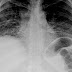

Chest X-rays are useful in the follow up routine of IPF patients. Plain chest X-rays are unfortunately not diagnostic but may reveal decreased lung volumes, typically with prominent reticular interstitial markings near the lung bases.

The radiological evaluation through HRCT is an essential point in the diagnostic pathway in IPF. HRCT is performed using a conventional computed axial tomographic scanner without injection of contrast agents. Evaluation slices are very thin, 1-2 mm.

Typical HRCT of the chest of IPF demonstrates fibrotic changes in both lungs, with a predilection for the bases and the periphery. According to the joint ATS/ERS/JRS/ALAT 2011 guidelines, HRCT is an essential component of the diagnostic pathway in IPF which can identify UIP by the presence of:

- Reticular opacities, often associated with traction bronchiectasis

- Honeycombing manifested as cluster cystic airspaces, typically of comparable diameters (3-10 mm) but occasionally large. Usually sub-pleural and characterized by well-defined walls and disposed in at least two lines. Generally one line of cysts is not sufficient to define honeycombing

- Ground-glass opacities are common but less extensive than the reticulation

- Distribution characteristically basal and peripheral though often patchy.